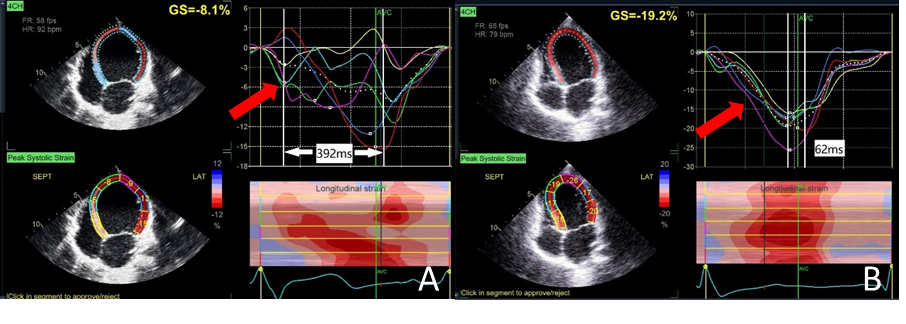

CLBBB儿童术前与术后心脏彩超的应变图形对比(红色箭头)A图为术前-应变曲线显示心室收缩杂乱无章;B图为术后-应变曲线显示心室收缩统一